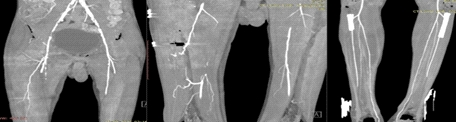

血管造影显示:右侧髂外动脉及股总动脉存在多灶性狭窄,其中髂外动脉狭窄程度至近乎完全闭塞,伴股浅动脉长段完全性狭窄;左侧髂外动脉及股总动脉亦存在多灶性狭窄,其中髂外动脉狭窄程度重度狭窄。

CT血管造影显示双侧下肢动脉弥漫性狭窄、管径减小,符合重度外周血管疾病(PVD)表现。尽管予以抗凝治疗并请血管外科会诊,患肢仍出现进行性斑纹及恶臭味,需行截肢术。